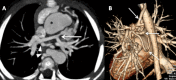

Congenital pulmonary artery anomalies represent a diverse group of abnormalities, ranging from asymptomatic incidental findings to causes of sudden cardiac death. While some may be recognized in childhood, others may be found incidentally in adulthood. We review the clinical and imaging findings in patients with congenital anomalies of the pulmonary arteries, including valvular and perivavular anomalies as well as abnormal narrowing, course and communications of the pulmonary arteries. We also discuss the role of various imaging modalities in the evaluation of these patients. It is vital to be aware of the key radiologic manifestations and associated haemodynamic consequences in these conditions in order to facilitate accurate diagnosis and prognostic stratification.